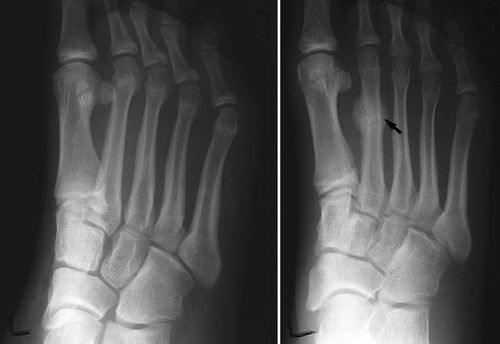

Hairline Fracture - अतिशय बारीक फ्रॅक्चर जे कधी कधी एक्स रे मधून दिसत नाही.

Stress Fracture - विशिष्ट भागावर नेहमी दबाव किंवा ताण पडून तुटणे. हे फ्रॅक्चर खेळाडूंमध्ये जास्त आढळून येते.